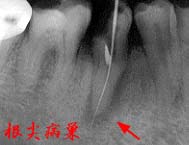

主訴の4|は、根管治療後の歯でパノラマ写真では明瞭な根尖病巣が確認できた。

クラウンおよびポストコアー除去後、通法に従って根管清掃を行い、出血や排膿がないことを 確認して即日充填を行った。翌日まで若干の疼痛が認められたものの、術後の経過は良好で、 根尖病巣部に存在した漏孔も1週間後には閉鎖。再びメタルコアーによる支台形成を行い、 最終補綴物を装着して同部の治療を終了した。

私の医院では、根尖部からの出血や排膿がない限り即日充填を基本としています。 根尖病巣の原因は、根管内に貯留した汚物に対するアレルギー反応に呼応したように 発生する根尖部の炎症です。原因となる汚物を機械的に(可及的)完全除去し、再び汚物が 貯留しないように死腔を(可及的)完全閉鎖すれば、根尖部の炎症は治まり破壊された 骨組織も根尖病巣の大きさに関係なく再生されます。